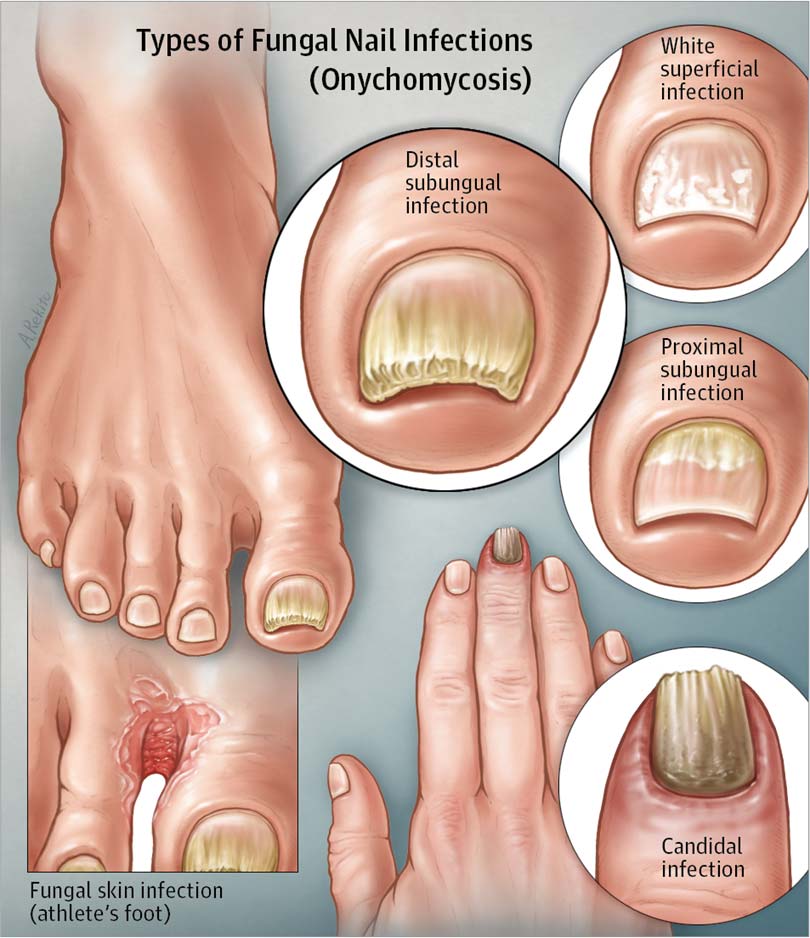

what does fungus on toe nails look like

What Is Fungal Infection (Mycosis)?

Foot fungus types pictures – Awesome Nail